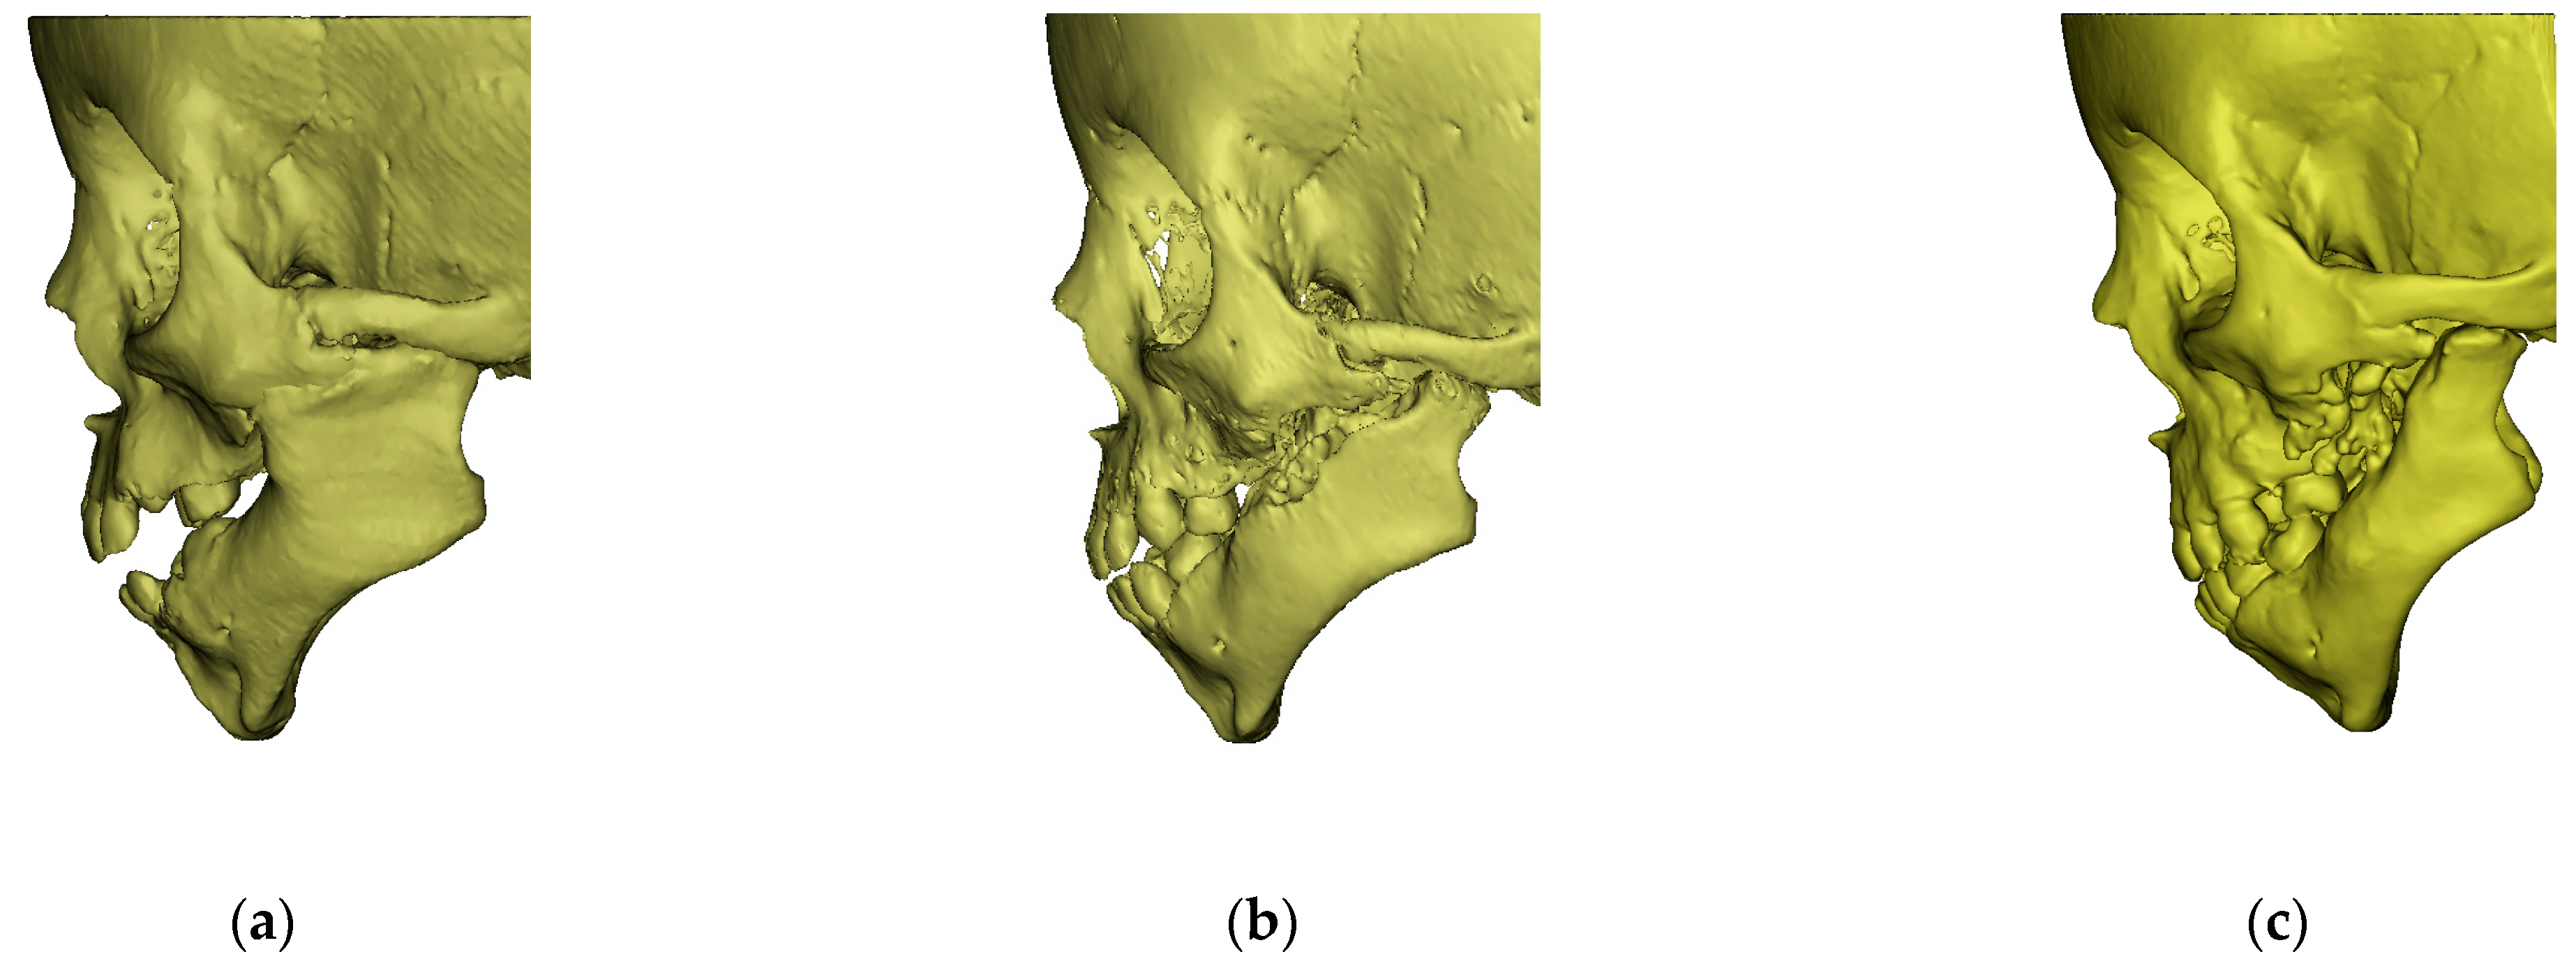

- left side larger than the right side; both the surface area and the volume were asymmetrical toa moderate degree (Table 4 and Table 5). Figure 4 shows the differences revealing asymmetrical structure of the mandibular bone in relation to the median sagittal plane. The greatest deviations from the symmetrical build exceeded 5 mm;

3.2. After the First Surgical Procedure and First Physiotherapy (Age—25 Months)

3.3. After Second Surgical Procedure and Second Physiotherapy (Age—54 Months)

- preserved symmetry of the length of both the entire mandible and the body (Table 5),

- moderate asymmetry of the body height at level M2 (Table 5);

- light asymmetry of the height of both rami (go–kdl), the right ramus was shorter than the left one (the operated one); an increase in growth on the operated side (Table 5),

- severe asymmetry of the gonial angles (alpha). The right-hand angle was larger than the left-hand angle by 11.88 degrees (Table 5).